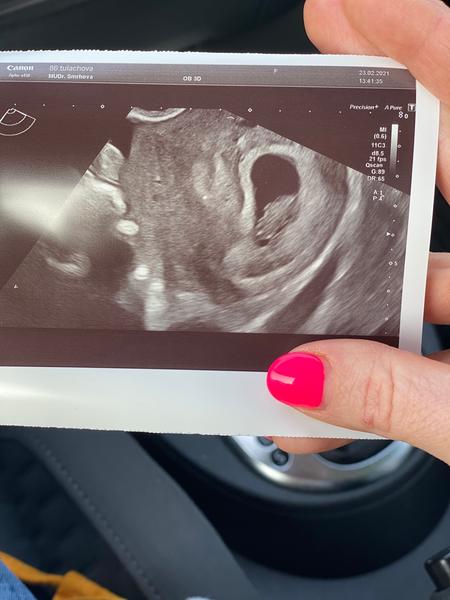

Já jsem 8+2 a můj UTZ vypadá teda úplně jinak, mám tam jakoby fazolku s náznakem hlavičky. Ta fotka co jsi dala je hodně malinké

@miskatus Teda, to už máte krásné 🙂 děkuji, snad se to brzy vyvine...